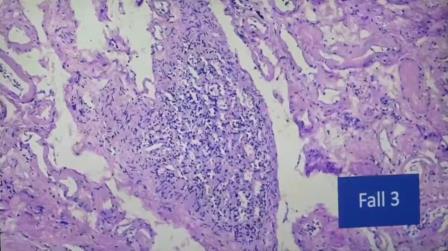

Pulmón

Daño alveolar difuso, no es alveolitis. Sólo se ven los linfocitos por el colapso

Aglomeración de linfocitos alrededor de un vaso

Incluso se ven los folículos, no deberían estar allí porque solo deberían estar en una reacción alérgica y aquí no hay nada exógeno, es endógeno

Esto todavía se está evaluando, todavía no se sabe, sobre todo como fenómenos del sistema autoinmune, reducción del sistema inmunitario, aceleración del crecimiento de tumores

Los grumos que forman los eritrocitos hasta que haya microtrombos. “No hemos visto microtrombos pero en sólo 10 pacientes es alarmante que se vea casos rarísimos como Sjörgen o Hashimoto”.